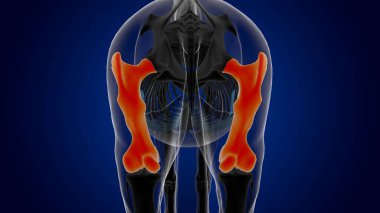

İnsan iskeleti anatomisi Scapula Kemiği Tıbbi Konsept için 3D Hazırlama

İskeletanatomiçene kemiğiyarım ayboyunlomberetmoidcapitateAltkısmınıHamate3d oluşturmaGöğüs kafesi3B illüstrasyoncarpalsağız sapımetakarplaralın kemiğiApendiküleruyluk kemiğioksipital kemikBurun kemiğikemiğigöğüs kemiğinin gövdesiayak kemikleriyarıçap kemiğiparietal kemikeksenel iskeletKalça kemiğilacrimal bonepalatine boneproximal phalangesinferior nasal conchaintermediate phalangesdistal phalangesclavicle bonekaval kemiğiBurun kıkırdağıkol kemiğikürek kemiğiBenzer İçerikler